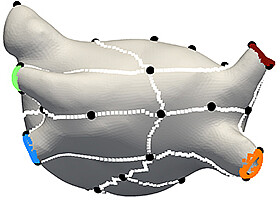

Herzmodelle zur Behandlung von Vorhofflimmern

Mit individuellen, digitalen Herzmodellen können Therapien getestet werden, um diejenige auszuwählen, die den größten Erfolg verspricht. Ein Verfahren des KIT erstellt aus klinischen Daten patientenspezifische virtuelle Abbilder des Herzens.